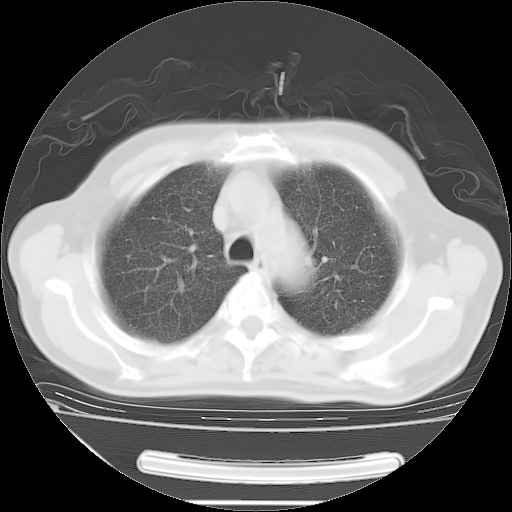

胸腹部CT,诊断意见:左上肺叶钙化灶、左侧胸膜局限性增厚并钙化、胆囊炎。描述部分肺组织呈磨玻璃样改变。